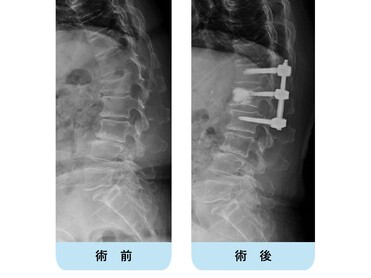

腰椎変性すべり症

変性すべり症は、腰椎が前後にずれてしまう病気で、中年以降の女性に発症しやすく、第4番目の腰椎によく認められます。多くは加齢とともに腰椎の椎間板や関節・靭帯がゆるみ、腰椎が不安定性をともなってずれるようになり、脊柱管が狭窄することで神経が圧迫されて、腰痛や下肢の痛み・しびれが生じます。

下肢の疼痛やしびれが強い場合は、神経ブロックなどを試みますが、これらの保存療法で改善の得られない症例では除圧術や脊椎固定術などの手術が必要となることがあります。

第4腰椎の前方へのすべりのため神経の圧迫を認めています。腰椎後方からずれを金属で整復固定し神経症状が改善しています。

階段状に腰椎が変性すべりをおこしている症例

【術前】

第2, 第3, 第4腰椎に前方への変性すべりを認めます。痛みのため背中を反って立てないことが分かります。MRIではいずれの椎間でも強い脊柱管狭窄が発生し、神経が圧迫されているのが分かります。

【術後】

スクリューとロッド、人工骨を使用した手術により腰椎の階段状変性すべりが整復され、痛みが改善したため腰を反って立つことが出来ています。第2腰椎の前方すべりは軽微であったため、金属は使わず除圧術のみに留めています。